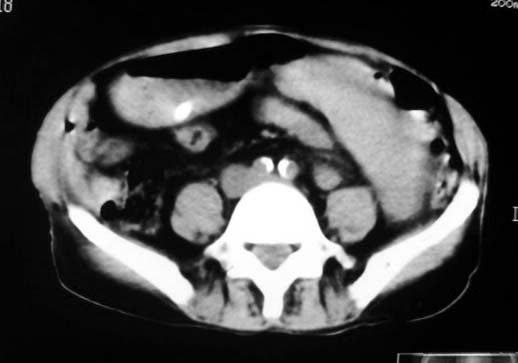

以下是引用dyqct在2007-4-20 16:38:00的发言:[br]考虑:1、巨脾;[br] 2、肝内多发低密度,首先考虑转移瘤;[br] 3、胆囊多发结石。

以下是引用andymaomao在2007-4-20 16:47:00的发言:[br]肝脾增大,肝内胆管扩张,且可见多发小囊性低密度灶,胆囊窝区高密度影,手术化疗病史,贫血....[br]1.肝脾大及贫血与术后化、药疗有关;[br]2.胆囊窝区高密度影,术后改变?肝内胆管扩张,积液?[br]3.肝内多发低密度灶,性质?建交增强